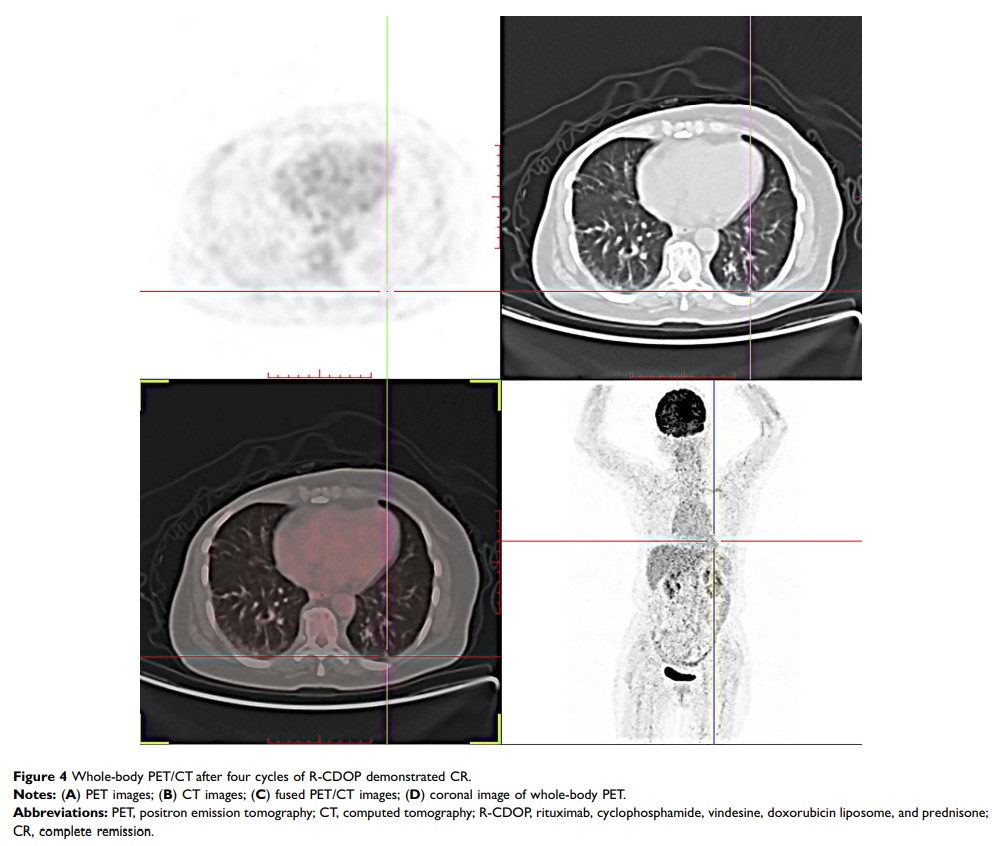

原发性肺弥漫性大 B 细胞淋巴瘤模拟转移:病例报告和文献综述